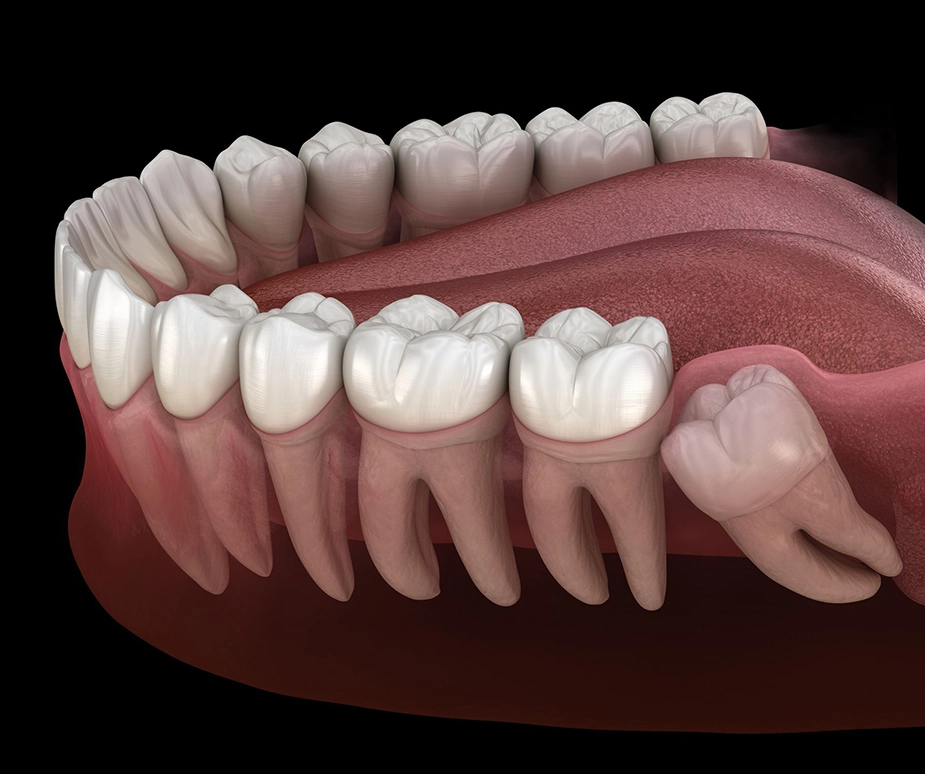

Wisdom Teeth Impaction

When wisdom teeth become impacted, they can cause a number of detrimental symptoms, including severe pain, swelling in the gums or around the jaws, bleeding gums, bad breath, strange tastes when eating, and even headaches. With that in mind, some individuals who have impacted wisdom teeth experience no symptoms at all.

Wisdom teeth impaction can occur to varying degrees. Soft tissue impaction is present when the top portion of the tooth (the crown) has come through the bone but is fully or substantially covered by the gum. A partial bony impaction involves a wisdom tooth that has partially erupted, but is still primarily below the gum tissue and inside the jawbone. A full bony impaction is a tooth that has not erupted and is completely covered by the jawbone.